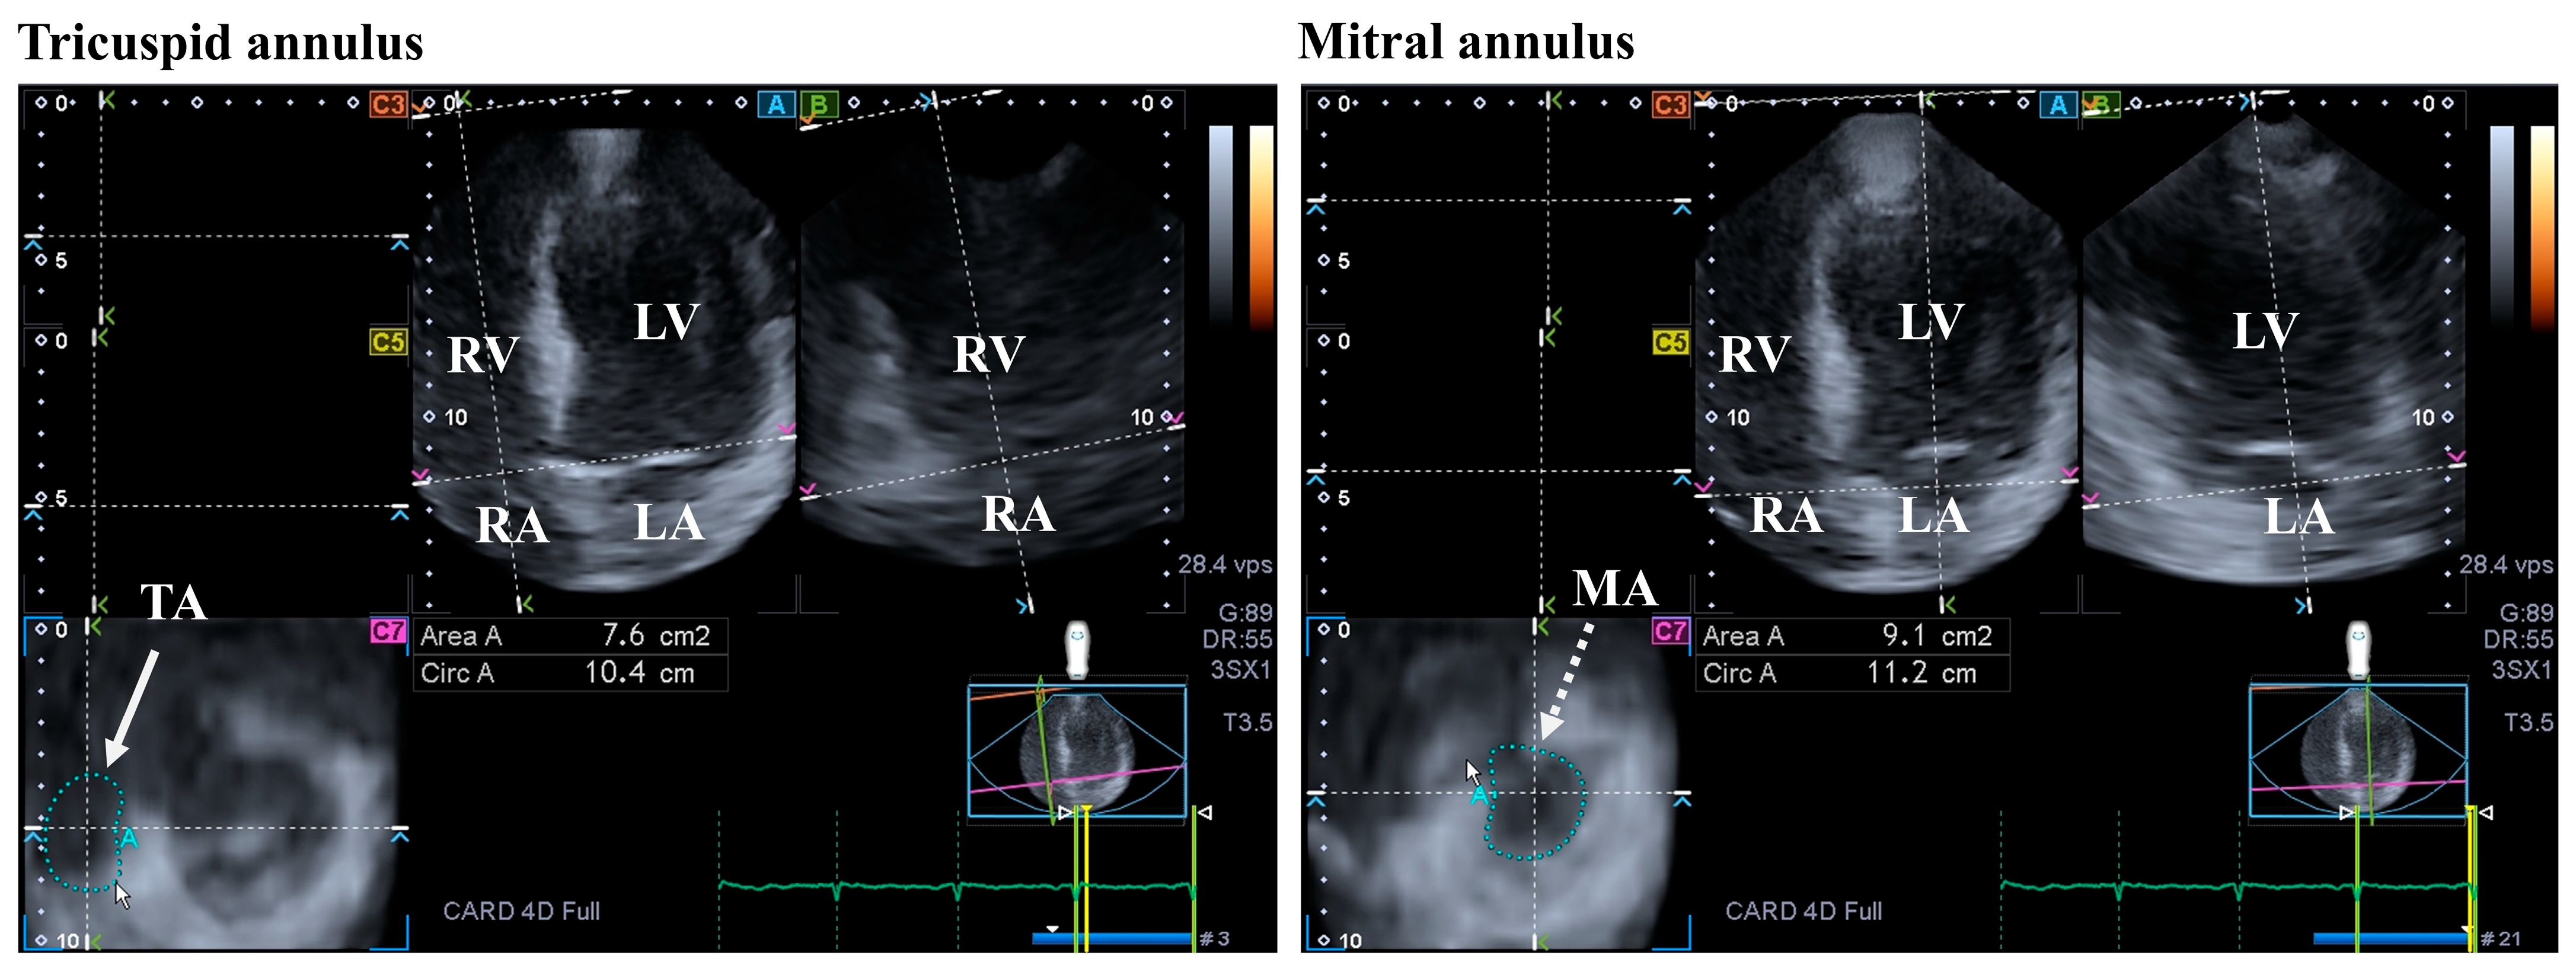

3.3. Mitral Valve

4.3. Tricuspid Valve

- Nemes, A.; Kormányos, Á.; Rácz, G.; Ambrus, N.; Marton, I.; Borbényi, Z. Mitral and Tricuspid Annular Abnormalities in Hypereosinophilic Syndrome—Insights from the Three-Dimensional Speckle-Tracking Echocardiographic MAGYAR-Path Study. Rev. Cardiovasc. Med. 2023, 24, 115. [Google Scholar] [CrossRef]